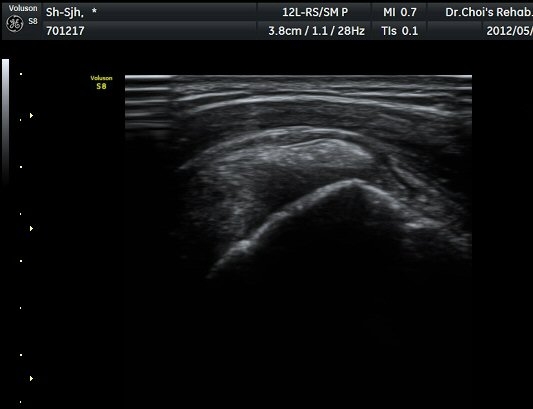

ÆÄ¿öµµÇ÷¯ °Ë»ç¿¡¼­ Ç÷·ùÁõ°¡¸¦ º¸ÀδÙ(»çÁø 6).  Ⱦ´Ü¸é°Ë»ç¿¡¼­µµ °í¿¡ÄÚ µ¢¾î¸®¿Í

Ç÷·ùÁõ°¡°¡ È®ÀεȴÙ(»çÁø 7, 8).